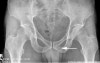

X-ray : 치골지 골절(Pubic ramus fracture)

X-ray 상 자세히 보지 않으면 역시 간과하기 쉬운 골절로, 실제 그냥 넘어지는 것만으로도 생길 수 있습니다.